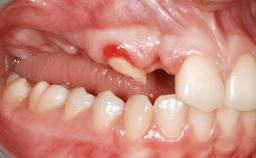

Iliac and Calvarial Bone Blocks for Onlay Grafting of a Severely Resorbed Edentulous Maxilla

A 45-year-old woman with a completely edentulous maxilla was referred to evaluate the possibility of rehabilitation with an implant-supported prosthesis. This patient was healthy and a non-smoker. She had been wearing a maxillary complete denture opposing a natural mandibular dentition since her twenties. This situation had resulted in progressive resorption of the alveolar ridge, repeatedly creating a need for relining the denture. Twenty years later, despite multiple adaptations and the use of “glues” the denture was unstable and causing the patient psychological and functional discomfort.

Bone Volume Horizontally and vertically sufficient Horizontally deficient Deficient vertically or deficient vertically AND horizontally

Bone Volume Deficient vertically or deficient vertically AND horizontally